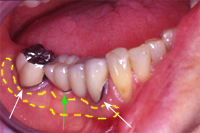

Die Abb. 1 bis 4 sollen als anschauliche Beispiele für gesunde und kranke Fundamente dienen.

Ein 31 Jahre alter Patient zeigt einen starke Zahnfleisch-Rückgang im Oberkiefer (Abb. 1 und 3) und wir beschliessen, diese Rezessionen zu behandeln.

Der Erfolg der Behandlung ist deutlich in den Abb. 2 und 4 zu sehen. Sehr augenfällig konnte die Situation um den Eckzahn im linken Oberkiefer verbessert werden (vergleiche dazu Abb. 3 vorher und Abb. 4 nachher).